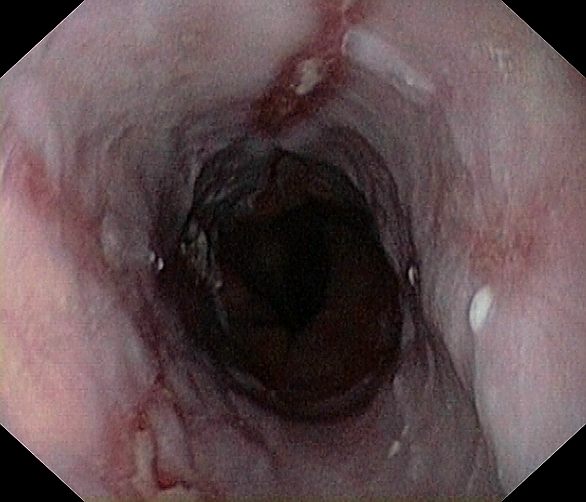

Reflux oesophagitis grade D according to the Los Angeles classification